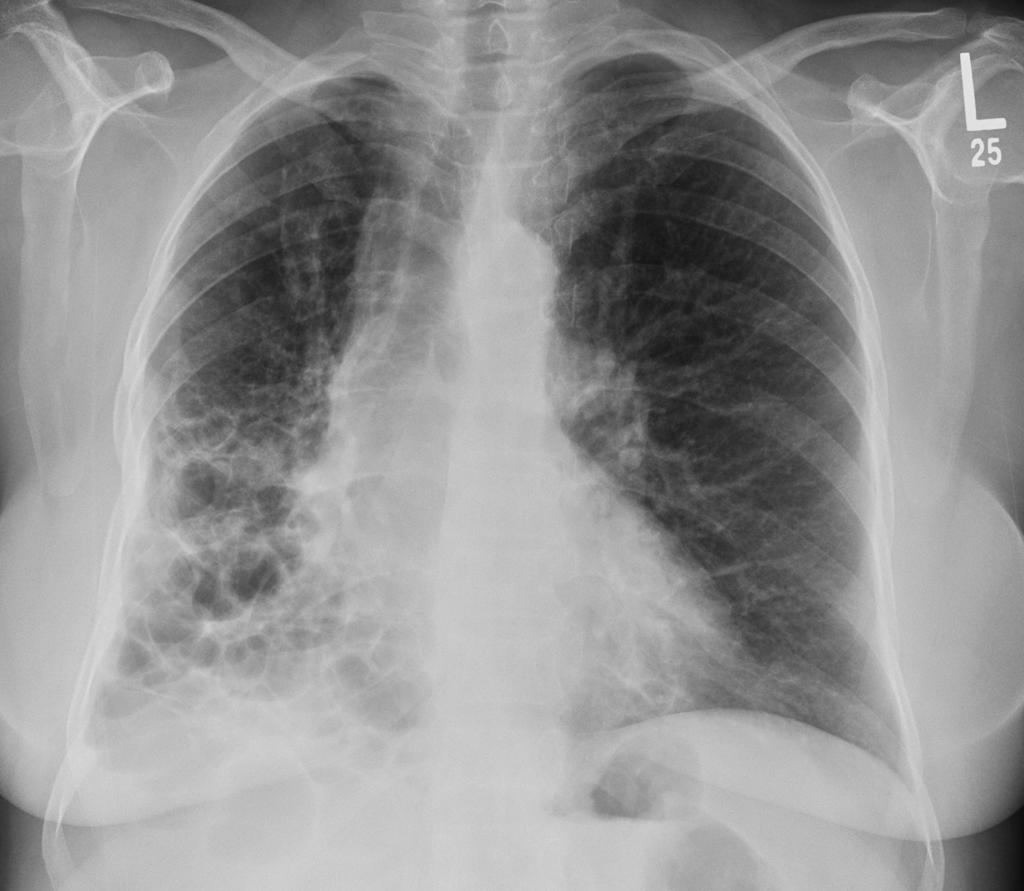

间质性肺疾病,简称ILD,听起来就像是肺部的"装修工程"出了问题

肺泡周围的间质组织发生炎症和纤维化,就像原本柔软的海绵变成了硬邦邦的石头,呼吸自然就困难了